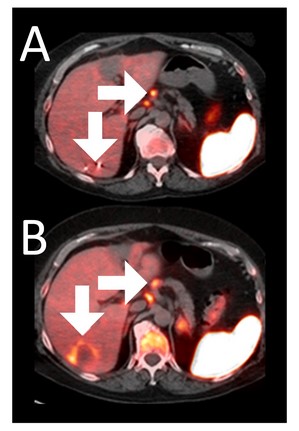

Example 3: Patient 15-006:

A 64-year-old woman with ER+/PR-/HER2- metastatic breast cancer, heavily pre-treated with 8 prior lines of therapy, including the antibody-drug conjugate Trodelvy, remains alive 25 months post-enrollment. At baseline, presented with hepatic metastasis.

Before BriaCell Treatment Image A: A liver metastasis (lower arrow) is “cold,” indicating minimal to no CD8+ cytotoxic T cells in the tumor while enlarged lymph nodes (upper arrow) show moderate uptake.

After BriaCell Treatment Image B: Swelling (induration) around the metastasis (lower arrow) demonstrates the liver metastasis has become “hot”, indicating marked CD8+ cytotoxic T cell infiltration while further lymph node enlargement is consistent with increased activity (upper arrow) indicating increased CD8+ T cells.

Example 3 Images (Patient 15-006): Combined MRI and CD8 ImmunoPET images Pre (A) and Post (B) Bria-IMT treatment